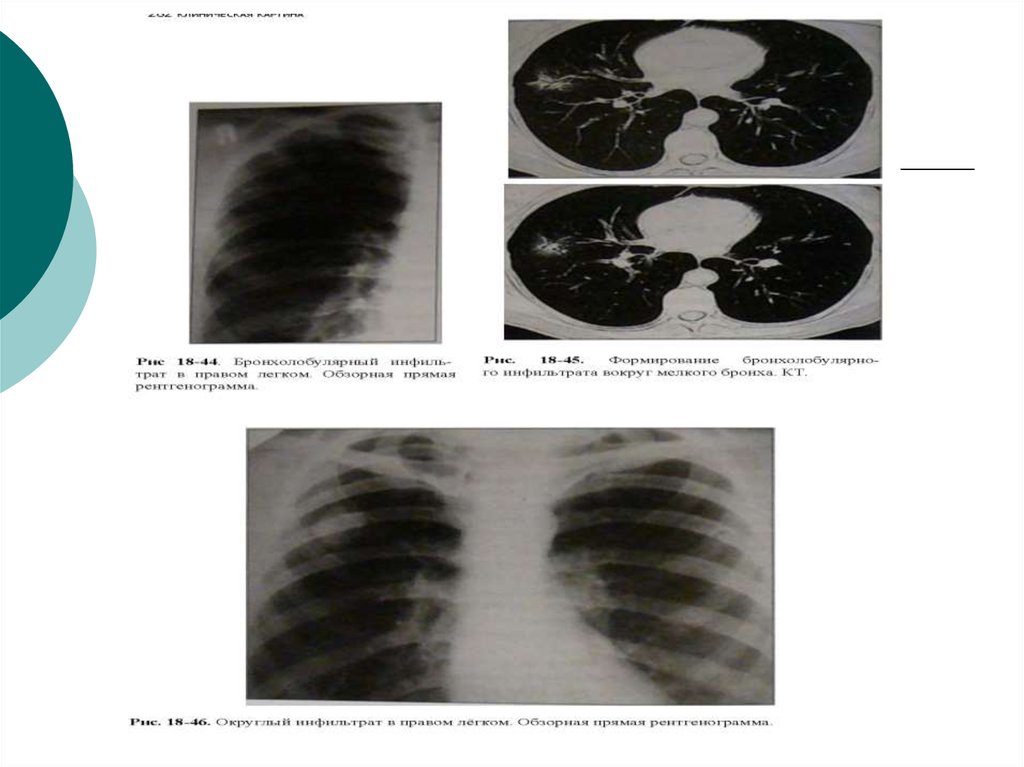

Симптомы и лечение инфильтративного туберкулеза легких

Раздел: Снимки-откровения